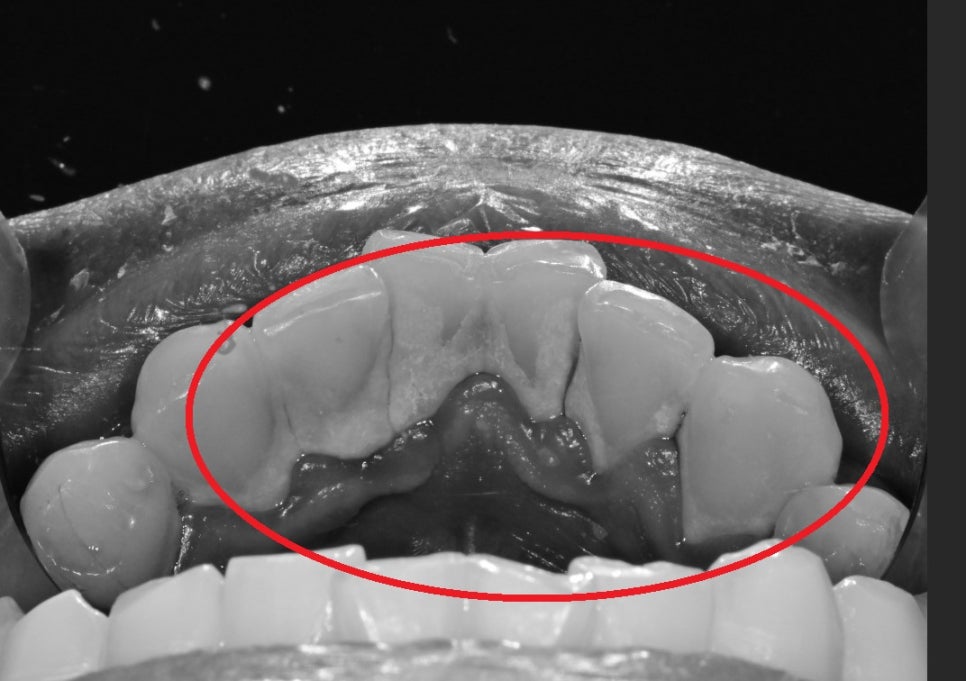

아래 치아 같은 경우

치열이 고르지 않다 보니 잇솔질이 효과적으로 되기 어렵고

치석이 잘 쌓일 수 밖에 없는 환경입니다.

어금니 쪽은 치아 사이가 충치가 진행되어

치아가 깨진 상태로

다발성 우식이 관찰되었습니다.